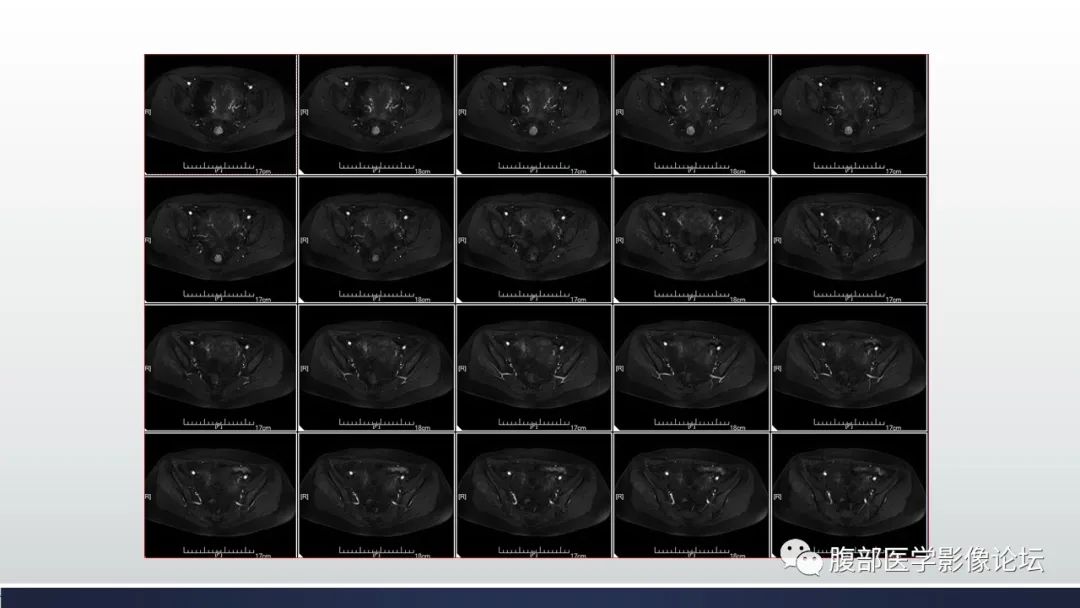

【病例】子宫内膜透明细胞癌1例MR-4